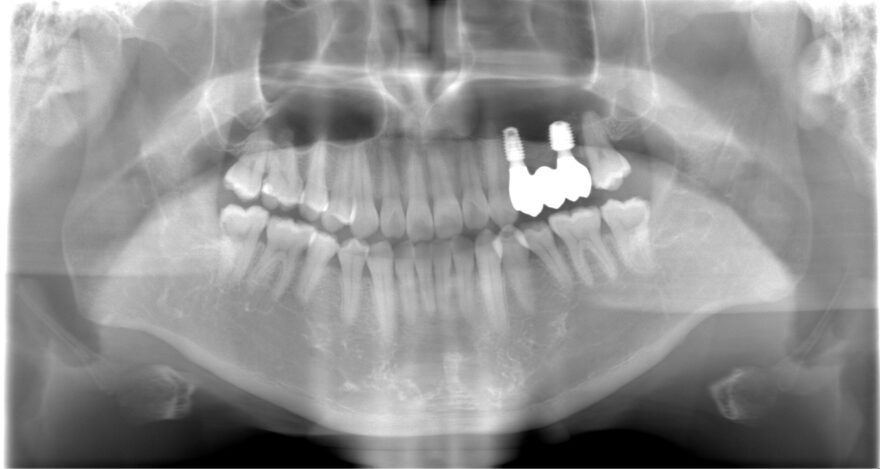

両サイドに2本のインプラントを埋め込み、3本の上部構造を支えるインプラントブリッジを患者様に提案しました。

埋め込むインプラントを3本ではなく2本にすることで、オペ後の腫れと痛みを少なく、治療費も少なくできます。

治療後のレントゲン写真

症例の治療に必要な標準的な費用

1,012,000円(税込)

奥歯インプラント2本→1本あたり440,000円(税込)

前歯プレミアムセラミックダミー2本→1本あたり132,000円(税込)